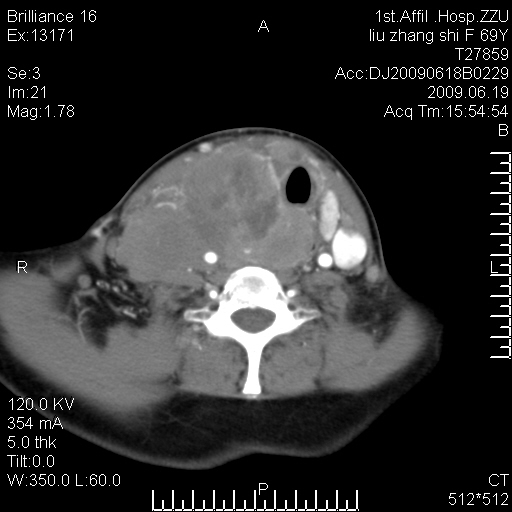

标题: CT26782:女,69岁,颈部占位,3天后公布病理结果。

【病理证实系列】女,69岁,颈部占位,有病理结果,3天后公布。(由于病例时间较久,临床资料不全,请网友见谅)本系列将有几百种常见、少见及罕见病例,均经病理证实。病例资料来自郑州大学第一附属医院。与网友共享,本人有空就发。

甲状腺癌并颈部淋巴结转移。感谢楼主的良苦用心,谢谢。

甲状腺癌并颈部淋巴结转移。

需与鼻咽癌鉴别!

支持甲状腺癌广泛侵及周围结构并颈部淋巴结转移。

鉴别:淋巴瘤、恶性神经源性病变、恶性纤维组织细胞瘤。

病理结果:颈部非霍奇金淋巴瘤。